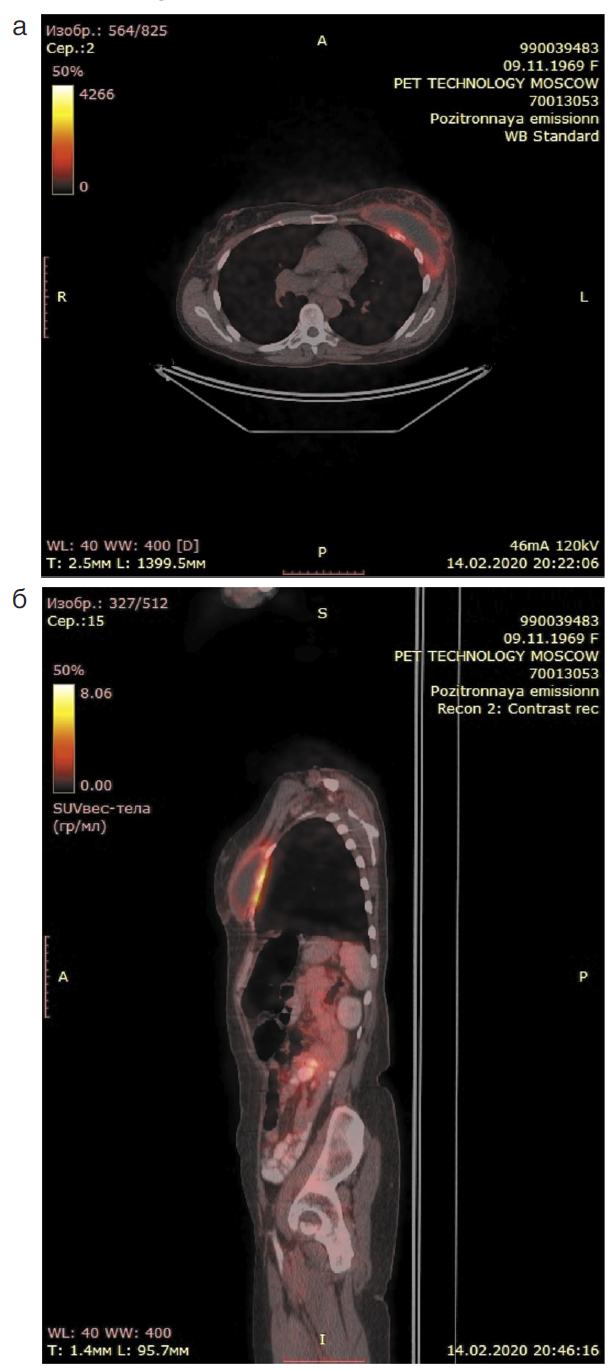

По данным комбинированной позитронно-эмиссионной и рентгеновской компьютерной томографии (ПЭТ-КТ) от 14.02.2020 слева под МЖ и грудной мышцей определяется структура жидкостной плотности с плотной капсулой с SUV 4.19 и в левой аксиллярной области – лимфатический узел до 20 мм с гиперфиксацией радиофармпрепарата. По капсуле вышеописанной структуры картина патологической активности от передних отрезков IV–V ребер слева (рис. 2).

Рис. 2. ПЭТ/КТ-проекции: а – аксиальная; б – сагиттальная. Определяется повышенная метаболическая активность F18-ФДГ в мягких тканях грудной стенки слева и в передних отрезках IV–V ребер слева.

Fig. 2. PET/CT projection: a – axial; b – sagittal. The increased metabolic activity with 18F-FDG is showed in the soft tissues of the left chest wall and in the anterior segments of IV–V ribs on the left.